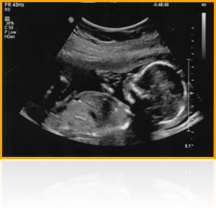

Suvidha Hospital provides ultrasound facility named by DEV ULTRASOUND. We provide ultrasound at high quality and at affordable rates. Ultrasound comes from a machine that creates an image of the inside of a pregnant women's body. It shows what a women's baby looks like while still inside her womb (uterus).

Ultrasound can tell you-and your health-care provider-many things about your baby, such as:

� The size of the baby

� How well the baby�s heart works

� How well other organs (such as the spine, brain and kidneys) are growing

� The anticipated date of birth